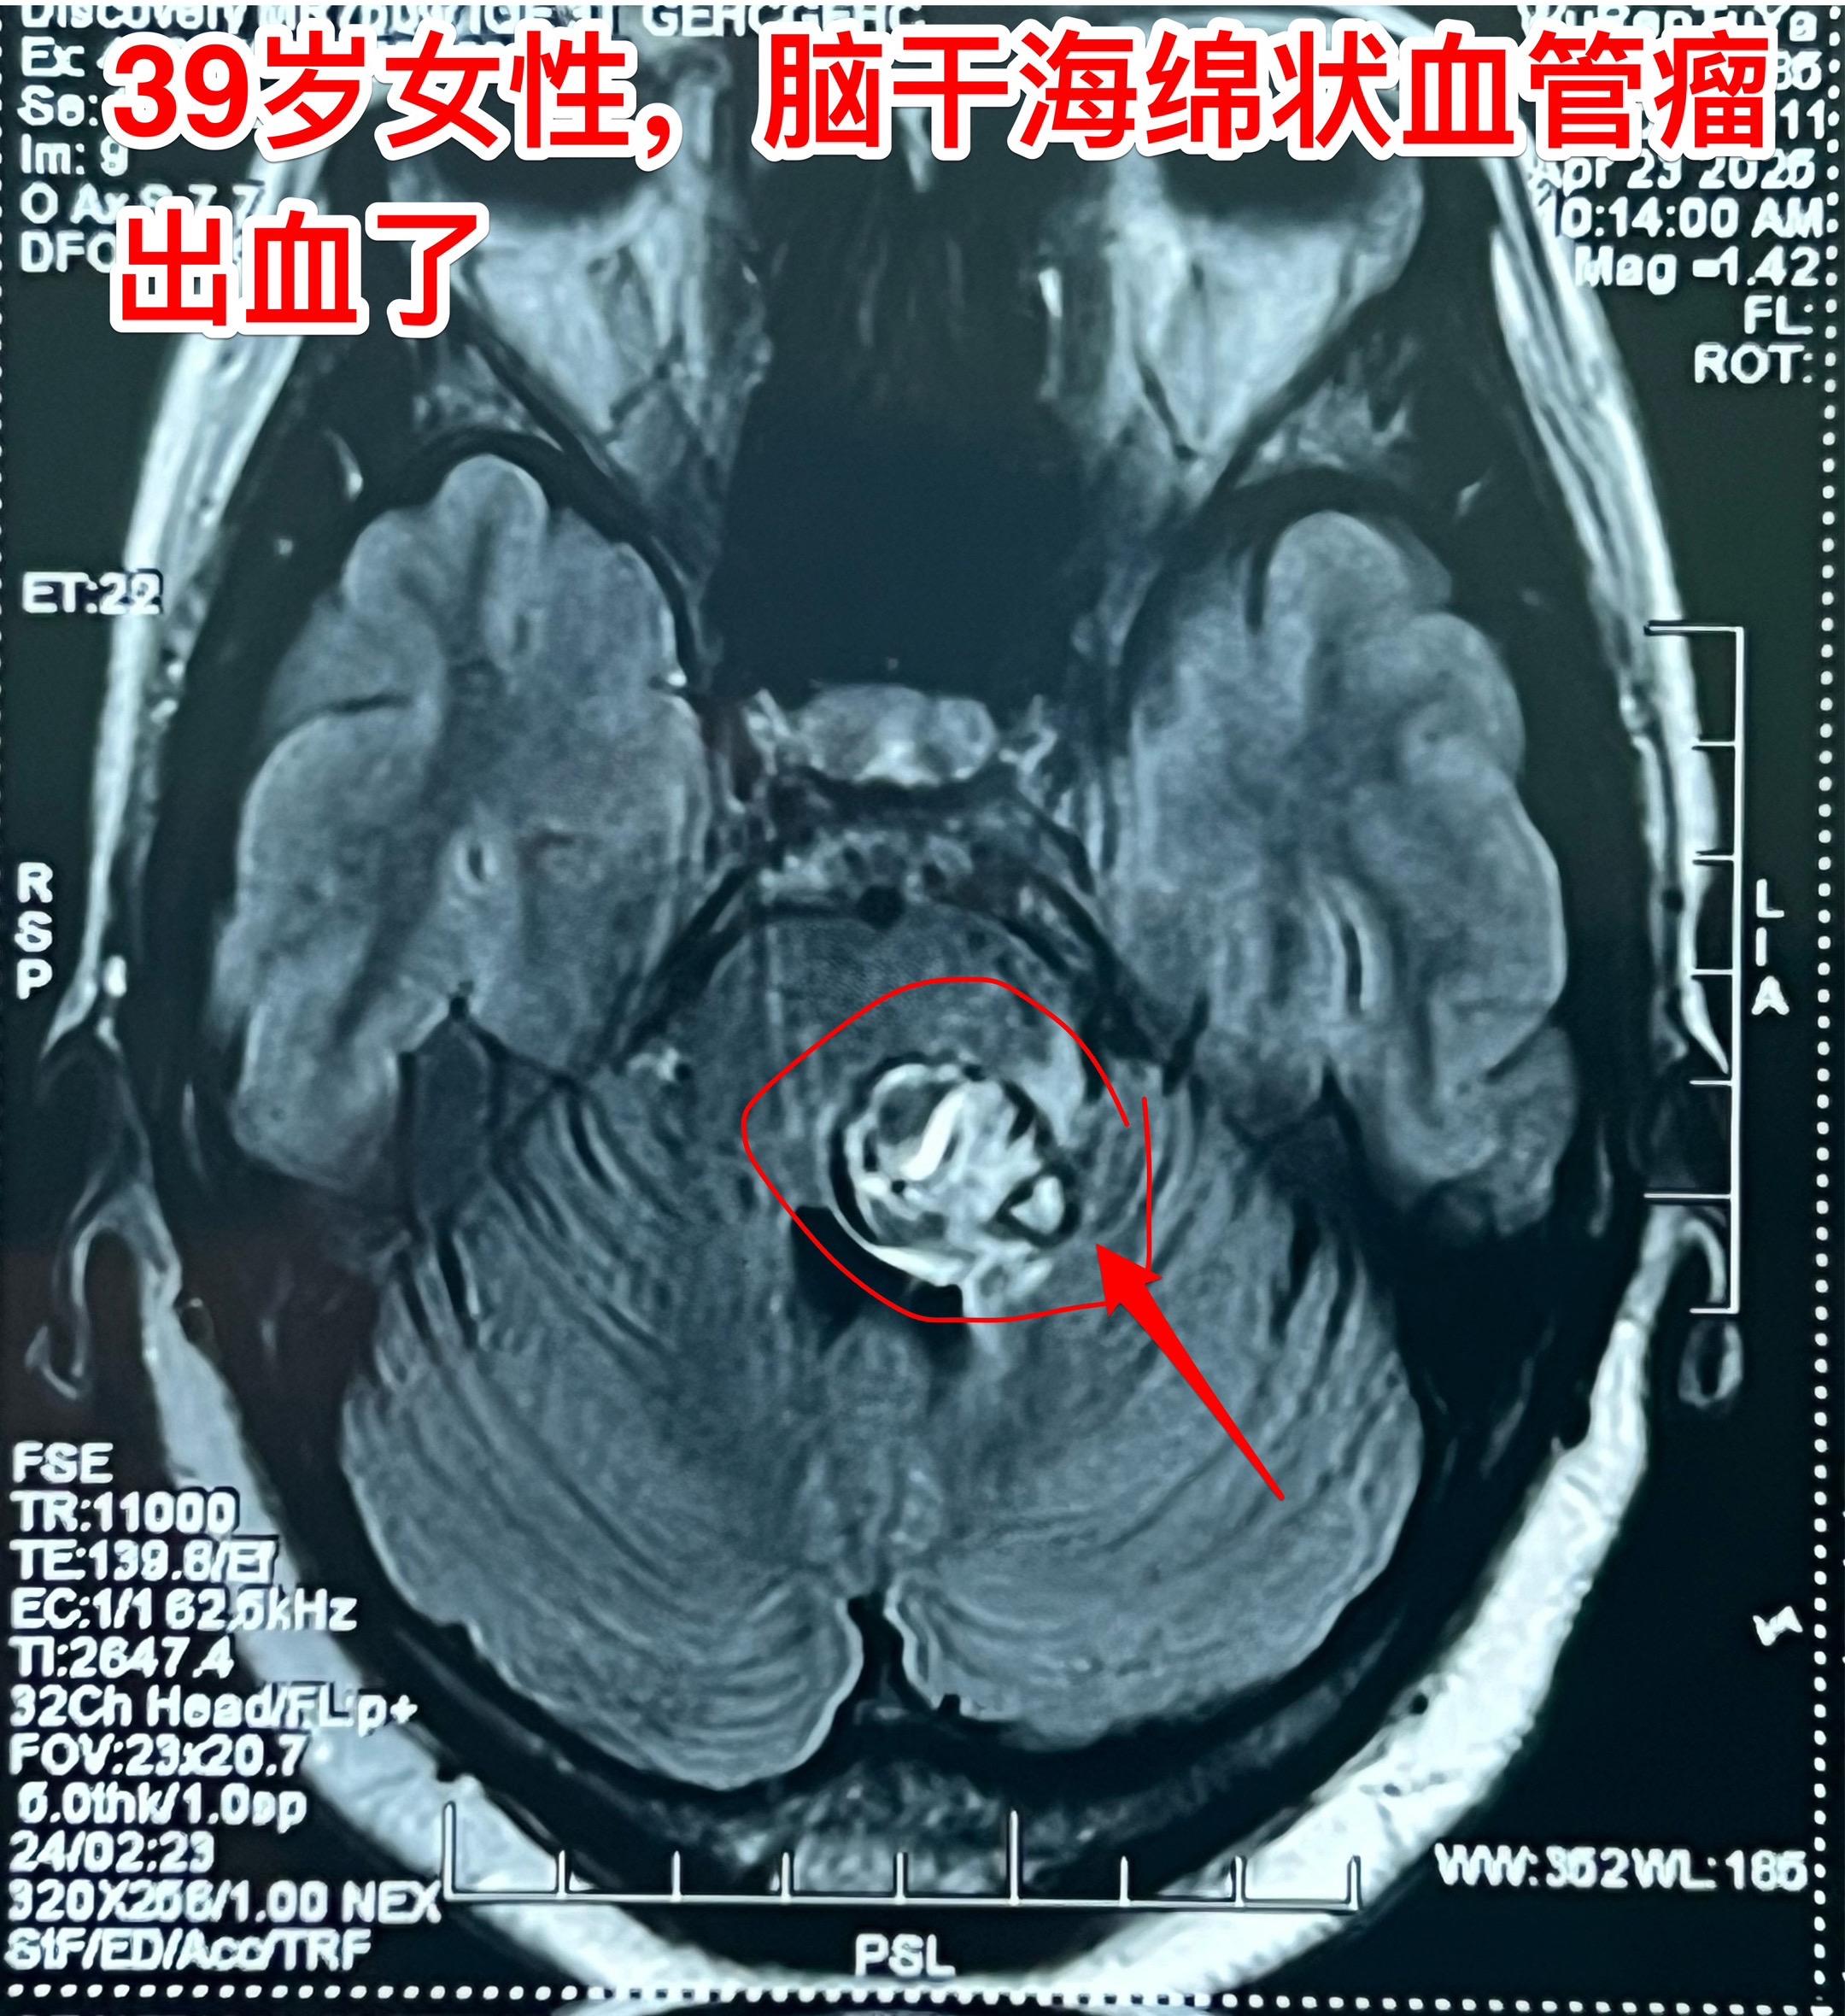

脑干海绵状血管瘤两次出血了—应该切除掉。39岁的蒙古族女性生活在内蒙古赤峰市的农业区,不过是真正的蒙古人。 近两年间断两次出现身体发麻。两年前曾经作 磁共振检查发现了脑干出血, 出血原因是海绵状血管瘤自发破裂。近期再次出现身体发麻,到医院检查发现脑干海绵状血管瘤再次出血了!如图所示,海绵状血管瘤直接大约2厘米,比两年前体积增大了,而且再次出血了。 这样的海绵状血管瘤就该作手术切除掉!尽管这个部位的手术难度很大。如果不作手术则很有可能再次出血,甚至导致病人昏迷或者成为植物人。